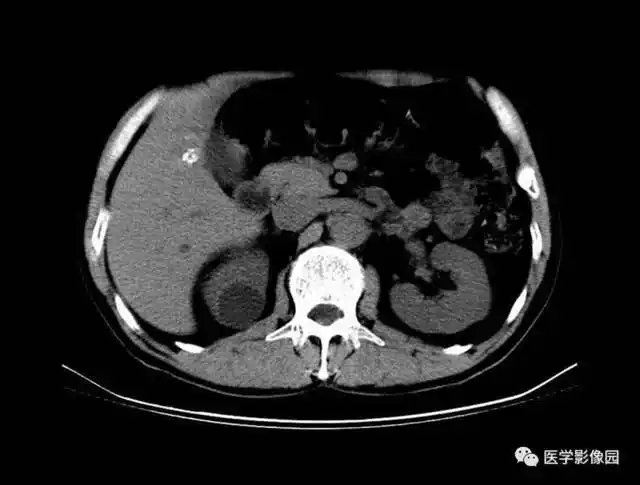

查体 辅查 腹部ct检查,发现左肾囊肿,大小约7*6cm

ct所见:右肾囊肿.

右肾囊肿ct